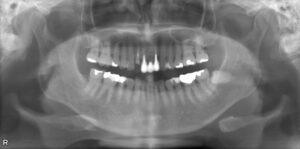

インプラント治療を成功させるうえで重要なのは、精密な治療計画です。そのためには顎の骨の状態を精密に把握する必要があります。そこで活躍するのが歯科用CTです。これまでのレントゲン検査とはくらべものにならないほどの詳細な情報を立体画像で確認することができます。

顎の骨の骨密度や厚み、さらに神経や血管の位置まで把握できるので、どの位置にどの角度でどれくらいの深さにどの種類のインプラントを埋入すればいいのかの綿密なシミュレーションが可能です。